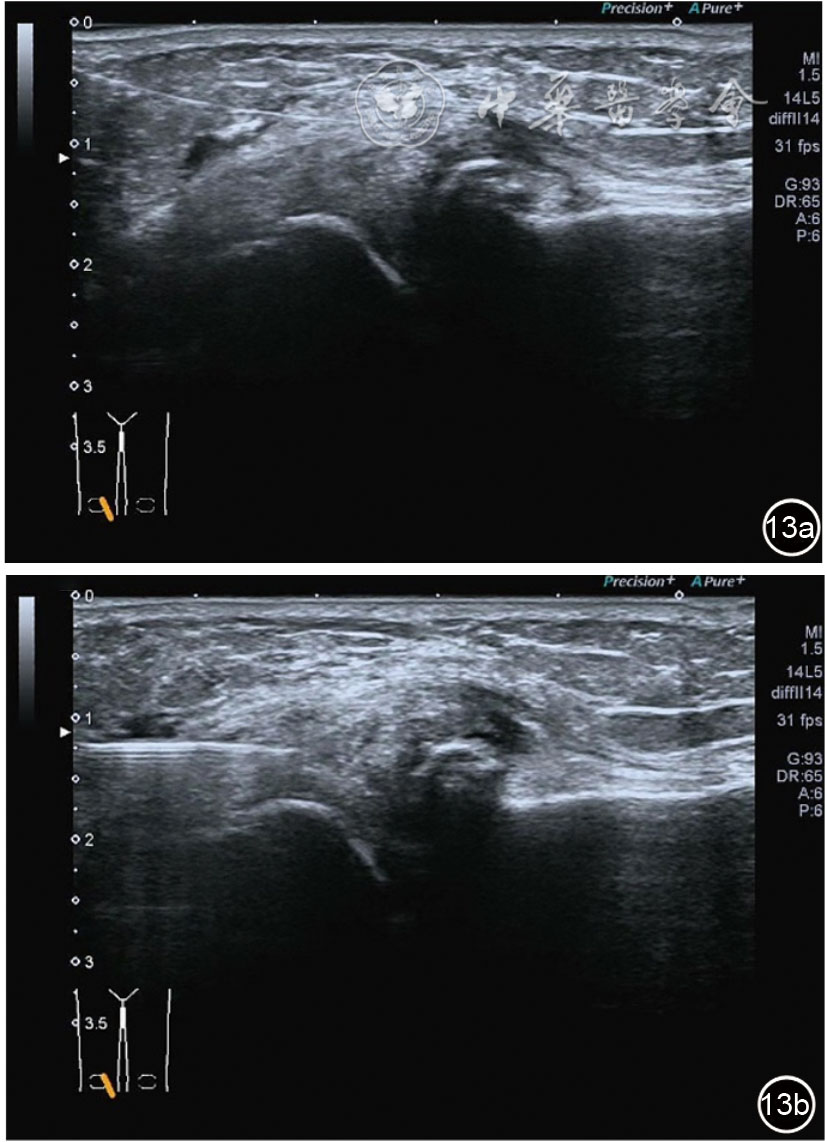

2.膝关节静态结构治疗。动力平衡失调后,继发静态结构变化,出现内外侧副韧带、交叉韧带、脂肪垫、半月板等结构变化。这里介绍半月板与交叉韧带的处理。(1)膝关节静态结构半月板治疗。在膝关节骨关节炎中主要是突出和损伤。突出主要发生于膝内翻引起的内侧半月板突出,引起内侧副韧带的张力增高。内侧半月板与内侧副韧带相连,是引起膝关节内侧疼痛的主要原因之一。治疗主要是针刀剥离松解,部分损伤可行PRP注射。①半月板突出针刀剥离松解治疗。针刀治疗主要是松解和减压,缓解疼痛,不能复位。以内侧半月板突出治疗为例。患者平卧位,髋轻度外展外旋,膝关节屈曲30°,膝下垫一软枕。选用10 MHz超声探头,穿刺区域常规消毒,探头涂抹耦合剂后套入无菌手套碘伏消毒或使用无菌耦合剂。将探头置于患者皮肤表面,内侧关节间隙长轴扫查,找到半月板突出最高点,用25G针头,抽吸1%利多卡因3 ml逐层麻醉直到半月板。选用直径1 mm的Ⅰ型2号针刀从头侧向足侧方向在内侧副韧带与半月板之间,以及半月板内部进行剥离松解3~5刀拔出针刀(图13),局部压迫5分钟,无菌敷料覆盖。②半月板损伤PRP注射治疗。半月板损伤主要表现为髌下痛,伸膝加重,查体在髌下髌韧带与侧副韧带之间,沿关节间隙有固定或局限性压痛,伸膝过程中尤为明显。MRI可示半月板断裂、损伤。如果出现绞索,严重影响功能需手术治疗。半月板损伤治疗,以注射PRP修复为主。以内侧半月板后角损伤为例。患者俯卧位,治疗前准备同半月板突出针刀剥离松解治疗。选用25G注射针头,抽取1%利多卡因2 ml局部麻醉后,制取1.5 ml PRP,穿刺到达半月板撕裂处注射,注射完毕后出针(图14),局部压迫2分钟,无菌敷料覆盖。(2)膝关节静态结构交叉韧带治疗。膝关节骨关节炎交叉韧带损伤多为部分损伤,治疗早期主要为药物或PRP注射,效果不佳时针刀做止点松解。①后交叉韧带损伤药物注射治疗。主要治疗韧带肿胀、无明显断裂患者。患者俯卧位,膝关节伸直位。一般选用10 MHz超声探头,治疗前准备同半月板突出针刀剥离松解治疗。将探头置于患者皮肤表面,后交叉韧带长轴扫查,找到胫骨止点,选用22G长针头,抽吸1%利多卡因3 ml+曲安奈德10 mg,从头侧向足侧方向穿刺到后交叉韧带胫骨止点部位的韧带表面进行注射,注射结束拔出针头(图15),局部压迫2分钟,无菌敷料覆盖。②前交叉韧带损伤PRP注射治疗。患者仰卧位,膝关节伸直。选用10 MHz超声探头,治疗前准备同半月板突出针刀剥离松解治疗。将探头置于患者皮肤表面,短轴扫查,找到前交叉韧带胫骨止点,选用25G针头,抽吸1%利多卡因3 ml逐层麻醉直到韧带止点部位,制备PRP 3 ml注射到前交叉韧带显露部位,注射结束拔出针头(图16),局部压迫2分钟,无菌敷料覆盖。③前交叉韧带损伤针刀剥离松解治疗。体位与治疗前准备同前交叉韧带损伤PRP注射治疗。短轴扫查找到前交叉韧带胫骨止点,选用25G针头,抽吸1%利多卡因3 ml逐层麻醉直到韧带止点部位,选用直径0.6 mm的Ⅰ型2号针刀从外侧向内侧于前交叉韧带胫骨止点部位剥离松解3~5刀拔出针刀(图17),局部压迫5分钟,无菌敷料覆盖。

图13 超声引导下半月板突出针刀剥离松解治疗